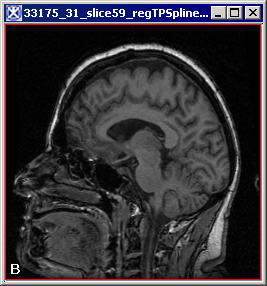

The input source image (A), the input target image (B) and the output registered image (C). Note that images (A) and (B) are both the images of the same brain. That's why it shows a very good overall fitting. Results may vary, if you take different brain images.